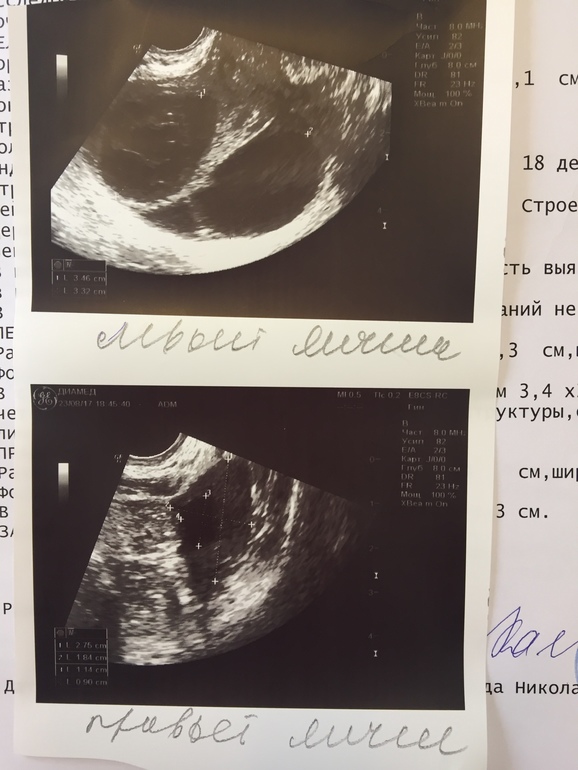

ФолликулометрияПривет мои девочки))))Ну может меня кто уже тут знает и иногда читает мои посты... а те кто нет, просто в крации расскажу).... В том месяце была неудачная стимуляция, было образование кист в левом яичнике. Во втором цикле т.е в этом )) на 12 дне была на УЗИ кисты чуть-чуть стали меньше, но не вышли с месячными(((( узистка увидела два ДФ в правом яичнике, врач мой сказала, давай делать завтра укол хгч 5000))) я сначала думала, переживала... Вам тут писала, но всё-таки решилась. На 13 дц вечером сделала укол... побаливал бок, думала ну все, она О, ух здорово. Вчера на 18 дц была на УЗИ... моя в отпуске, поехала аж в другой город на УЗИ... по дороге думаю, ну будь, что будет... ну скажет что все плохо, ну что ж теперь...Ну короче, я легла... она мне говорит... Оооо у тебя два замечательных ЖТ в левом яичнике! Я смотрю на неё, слушала... слушала ... и говорю!!! У меня это так кисты... ещё с прошлой О. Аааа, ну да похожи на кисты... и тут я поняла "приплыли"... говорю у меня два ДФ было с права, посмотрите что там... смотрит и говорит... у тебя сейчас один фоллик 1,3 см! Желтого тела нет! Я говорю, а где второй, ну может овуляция произошла, лопнул... говорю, а ЖТ нет же! Ааа, ну да... я говорю, может сдулся? Ну, может... вот после этого я просто встала молча, взяла бумажки и ушла... в голове дурдом! Ехала всю дорогу и переваривала... думаю, может сдулся, может она фоллик перепутала с ЖТ? Господи ей около 50 лет, и я не услышала внятного никакого ответа. Короче у меня и в этом цикле пролёт. Прилагаю Вам УЗИ и фото. Посмотрите. Плюсом приложу Вам УЗИ, которое делала на 12 Дц.